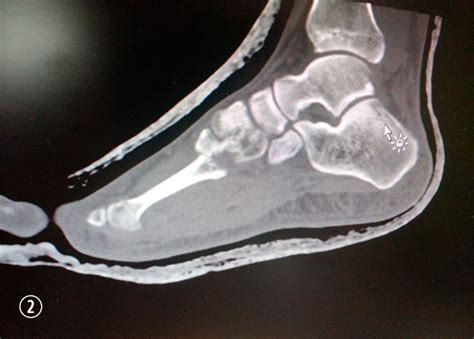

WebLaincapacidad permanente por artrodesises una situación médico – legal cada vez más frecuente en el momento de reclamar la declaración de nuestro grado de. WebEn función de ello, el grado de minusvalía por artrosis de rodilla puede ir desde un 7 a un 50%, debiendo tenerse especialmente en cuenta si la artrosis de rodilla afecta a los. WebSi se ha diagnosticado artrosis de rodilla a una persona, se le puede asignar un grado de minusvalía para ayudar a determinar el nivel de discapacidad y los beneficios a los que. WebUn grado de minusvalía es una designación legal que se usa para describir el impacto que una discapacidad o enfermedad tiene en la vida diaria de una persona. Los. WebLa artrodesis total de muñeca, también conocida como fusión de muñeca, es un procedimiento quirúrgico en el que se estabiliza o inmoviliza la articulación de la. WebEn el caso de que la artrosis afecte a una sola articulación, se suele otorgar una minusvalía del 10%. Si afecta a más de una articulación, el grado de minusvalía puede. Web¿Cuáles son los grados de minusvalía por artrosis? GRADO 0: NORMAL – En el grado 0 o normal, no existe ningún tipo de dolor, ya que se considera que se encuentran en este. WebEl grado de discapacidad por artrosis de rodilla o el grado de minusvalía por artrosis de cadera, por ejemplo, depende de las circunstancias que te exponemos. Sólo.

WebIncapacidad absoluta por artrodesis lumbar y lumbociatalgia crónica. En Fidelitis celebramos el reconocimiento de una pensión de incapacidad permanente absoluta en. WebContestado. Buenos días, Debe esperar al final de la operación y luego solicitar la prestación de incapacidad, para ello debe de pasar un Tribunal médico el cuál le. WebLa incapacidad permanente por artrodesis es una realidad médico – legal cada vez más frecuente a la hora de reclamar la declaración de nuestro grado de incapacidad.